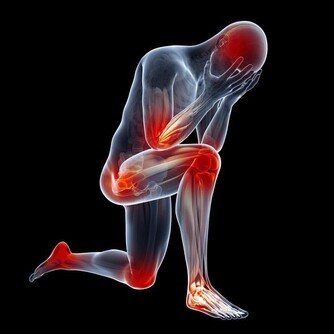

說到痛風,很多人第一印像是膝蓋、腳後跟、腳大拇指等地方疼痛,到醫院一查,尿酸高了!

痛風是由單鈉尿酸鹽沉積所致的晶體相關性關節病,與嘌呤代謝紊亂和(或)尿酸排泄減少所致的高尿酸血症直接相關,特指急性特徵性關節炎和慢性痛風石疾病。

主要包括急性發作性關節炎、痛風石形成、痛風石性慢性關節炎、尿酸鹽腎病和尿酸性尿路結石,重者可出現關節殘疾和腎功能不全。

痛風是長期嘌呤代謝障礙,導致體內長期尿酸增高,會在局部形成尿酸結晶,特別是下肢的足背小關節,會導致痛風性關節炎,或是直接形成痛風石,從而會刺激關節面引起反复的疼痛。其臨床特點就是高尿酸血症。但在疼痛急性發作期並不一定的尿酸最高時。